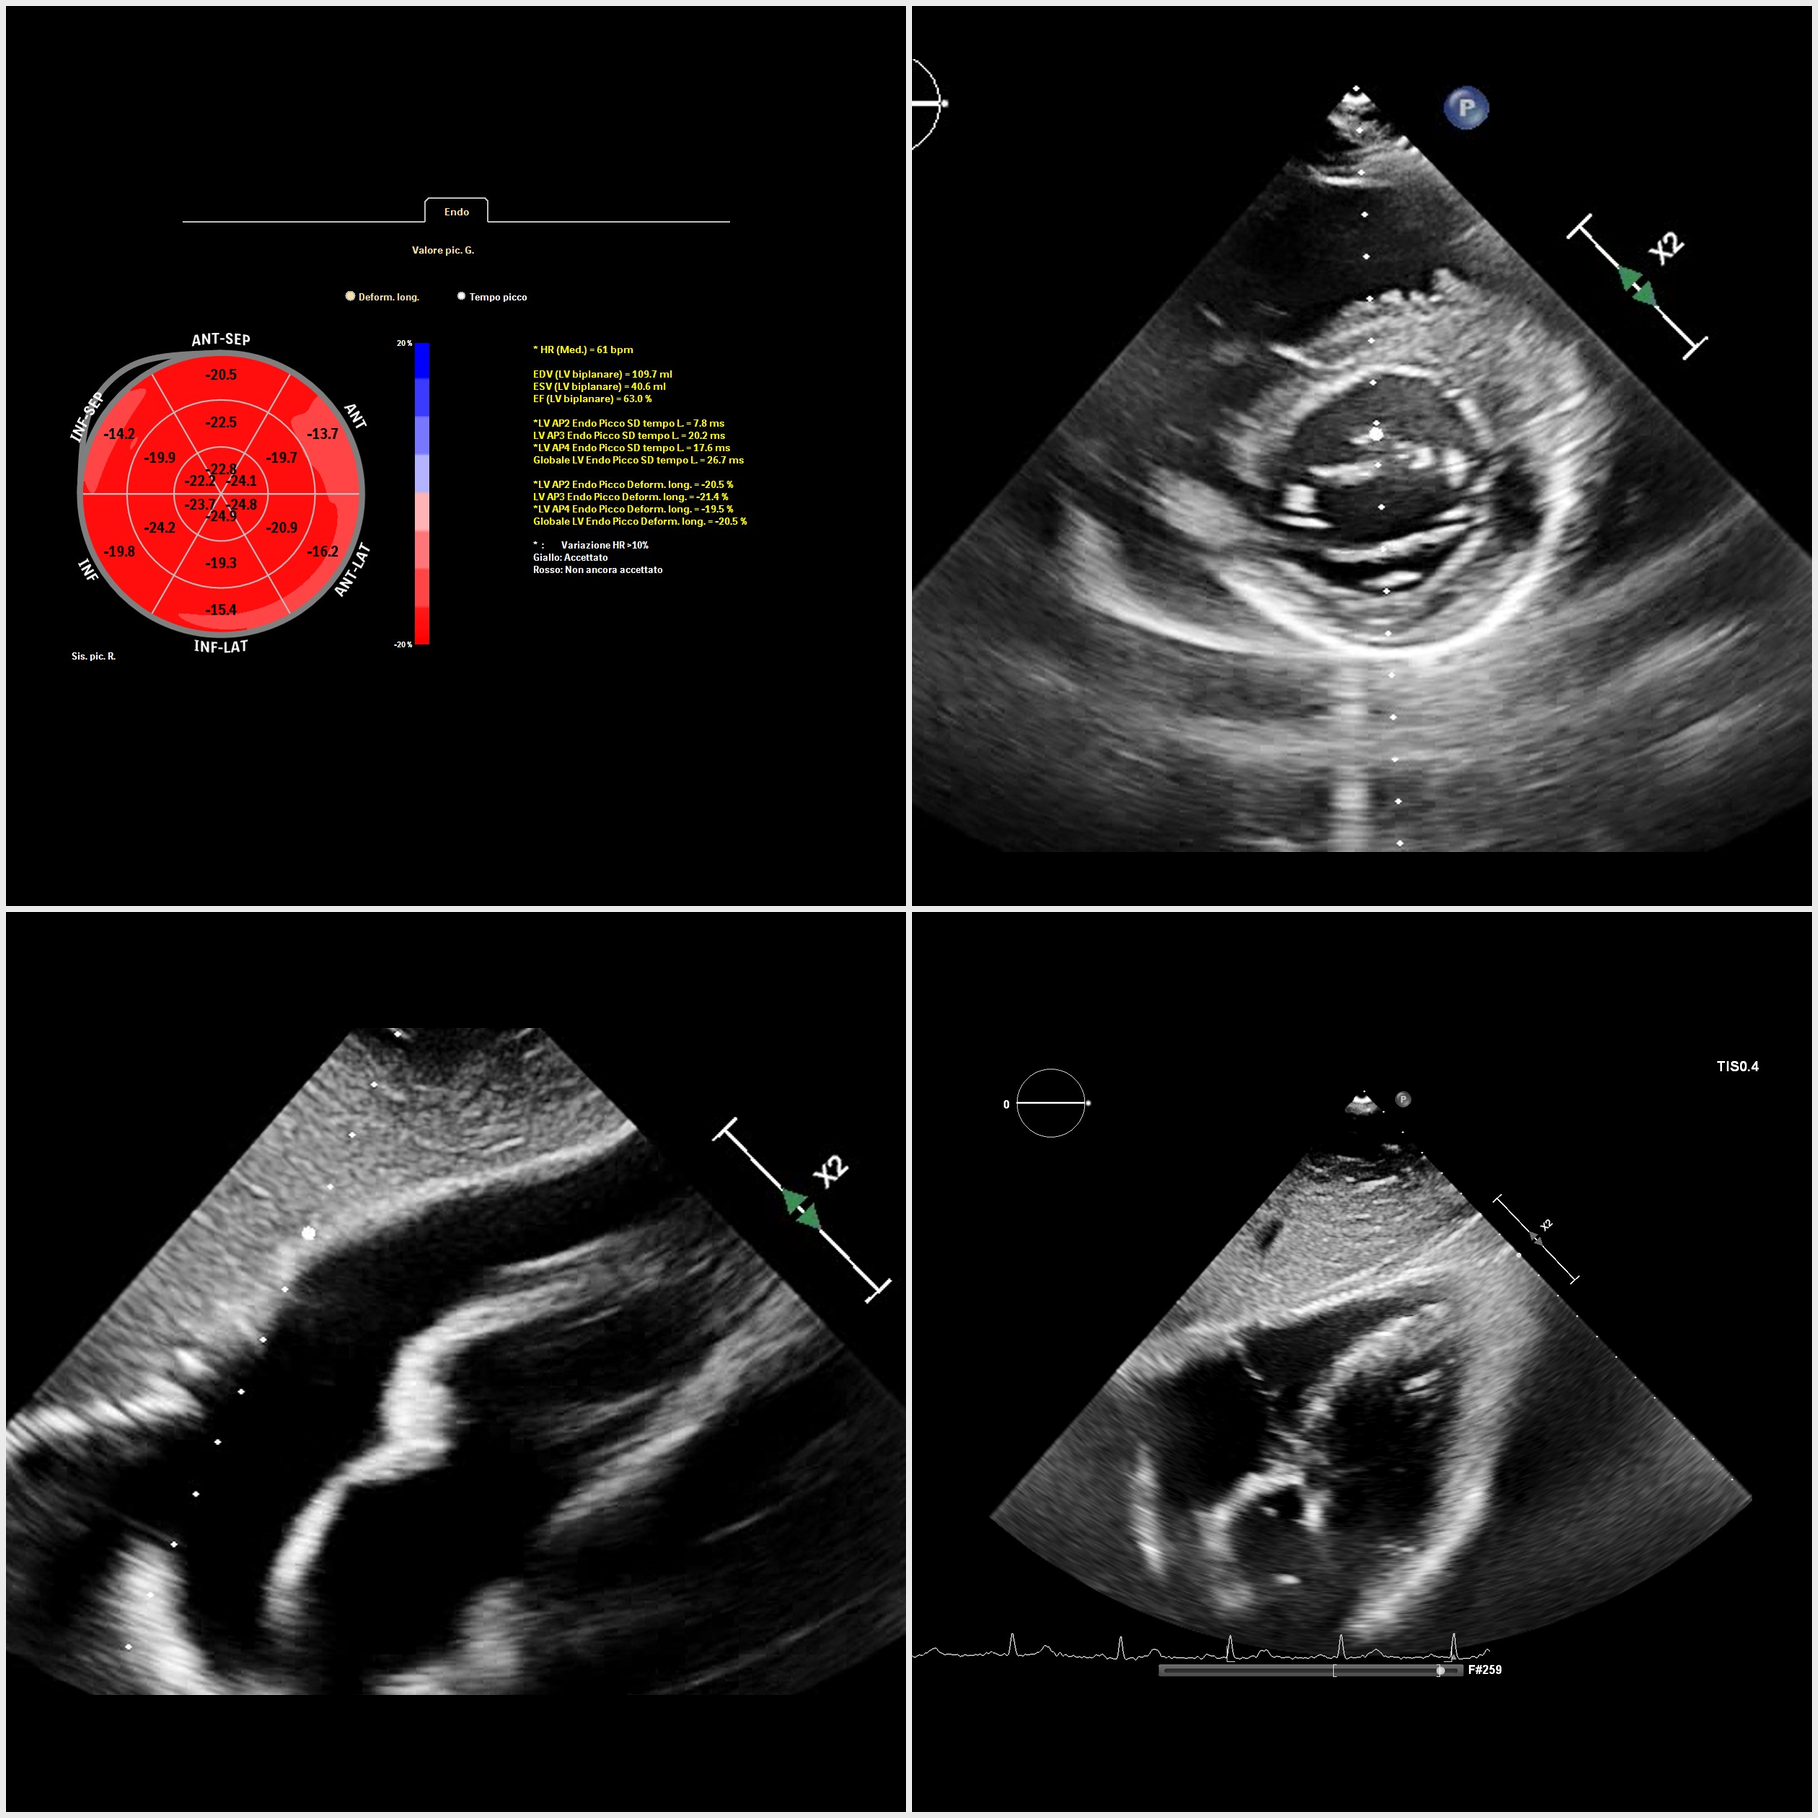

Background: Cardiac involvement in hematologic malignancies is uncommon and often subclinical; it may present with pericardial effusion and myo-pericardial infiltration. Case presentation: A 41-year-old man with relapsed acute lymphoblastic leukemia (prior chemotherapy and two bone-marrow transplant attempts) was referred for hypotension and marked asthenia. He denied chest pain, palpitations, and syncope. ECG showed sinus rhythm, anterior T-wave inversion, and low QRS voltages. Laboratory tests revealed mild anemia and leukocytosis. Urgent echocardiography demonstrated a large circumferential pericardial effusion with pre-tamponade signs (right atrial collapse, marked respiratory variation of transtricuspid inflow) and a dilated, poorly collapsible inferior vena cava; biventricular function was otherwise preserved. Diagnostic-therapeutic pericardiocentesis drained >1,000 mL of frankly hemorrhagic fluid; cytology was positive for malignant cells. CMR showed mid-basal LV wall thickening (anterior/anteroseptal/inferoseptal) with mild T2-STIR hyperintensity and increased T1/T2 mapping values, consistent with myo-pericardial leukemic involvement. Infiltrating tissue was detected along the anterior interventricular groove encasing the left main and LAD, extending to the left atrial anterior/lateral walls and surrounding the circumflex, and reaching the aorto-pulmonary window in close contiguity with the main pulmonary artery; ventricular function was preserved. Speckle-tracking echocardiography showed normal global longitudinal strain with regional reduction in basal anterior, anterolateral, inferolateral segments and basal inferior septum. During ongoing hemato-oncologic therapy, the patient has remained asymptomatic, without recurrent pericardial effusion and with stable echocardiographic parameters. Discussion/Conclusions: A hemorrhagic pericardial effusion with positive cytology may be the first clue of cardio-pericardial infiltration. Regional strain abnormalities can support escalation to advanced imaging; CMR is pivotal for non-invasive tissue characterization and diagnostic confirmation.